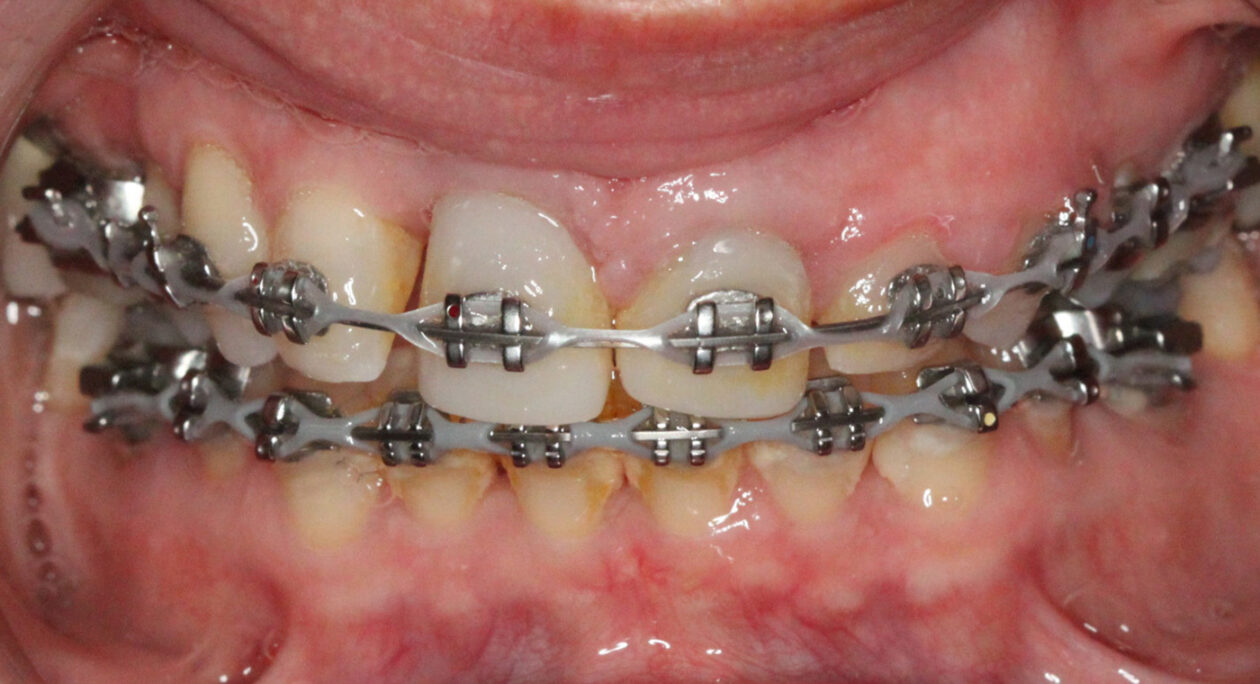

Extraction after forced eruption can allow for a much more favorable implant site compared with extraction alone. This is possible because the tension applied to the periodontal ligament during orthodontic tooth movement stimulates osteoblastic activity to induce new bone formation. As the tooth moves coronally during extrusion, soft tissue and bone attached to the periodontal fibers migrate in the same direction. As a result, forced eruption can be used to enhance the quality and quantity of both hard and soft tissue of future implant sites.

The special report presented below illustrates how orthodontic extrusion was successfully used to improve the periodontal architecture prior to the placement of two adjacent implants in the esthetic zone and thus allowed for a more ideal restorative result.